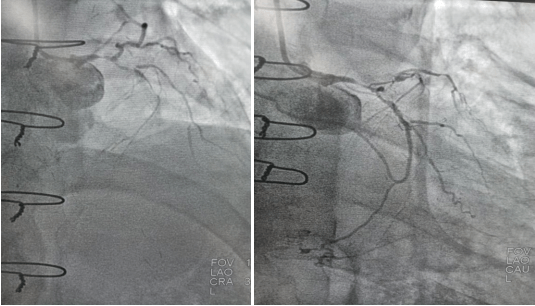

2022年9月16日行冠脈造影術,造影結果示:左主干末端99%狹窄,LAD近段100%閉塞,LCX開口及近段95%狹窄,乳內動脈-左前降支血管通暢,RCA近段100%閉塞,大隱靜脈橋血管未見,考慮閉塞。

心血管病院吳棟梁院長、CCU李新國副主任、心血管內科二病區趙娟副主任、王端樂主治醫師、宋睿主治醫師介入團隊造影后認真研究患者的病情和影像資料,決定開通閉塞長達11年的右冠狀動脈,精確選擇器械,選擇同軸性及支撐力均好的指引導管,術中選用微導管輔助,軟、硬導絲結合等技術,聚精會神、揮汗如雨,終于歷經3小時的努力,成功前向開通右冠狀動脈,精準選擇由遠及近“鋪設”通過性較好、長度合適的支架 。

(術前術后對比)